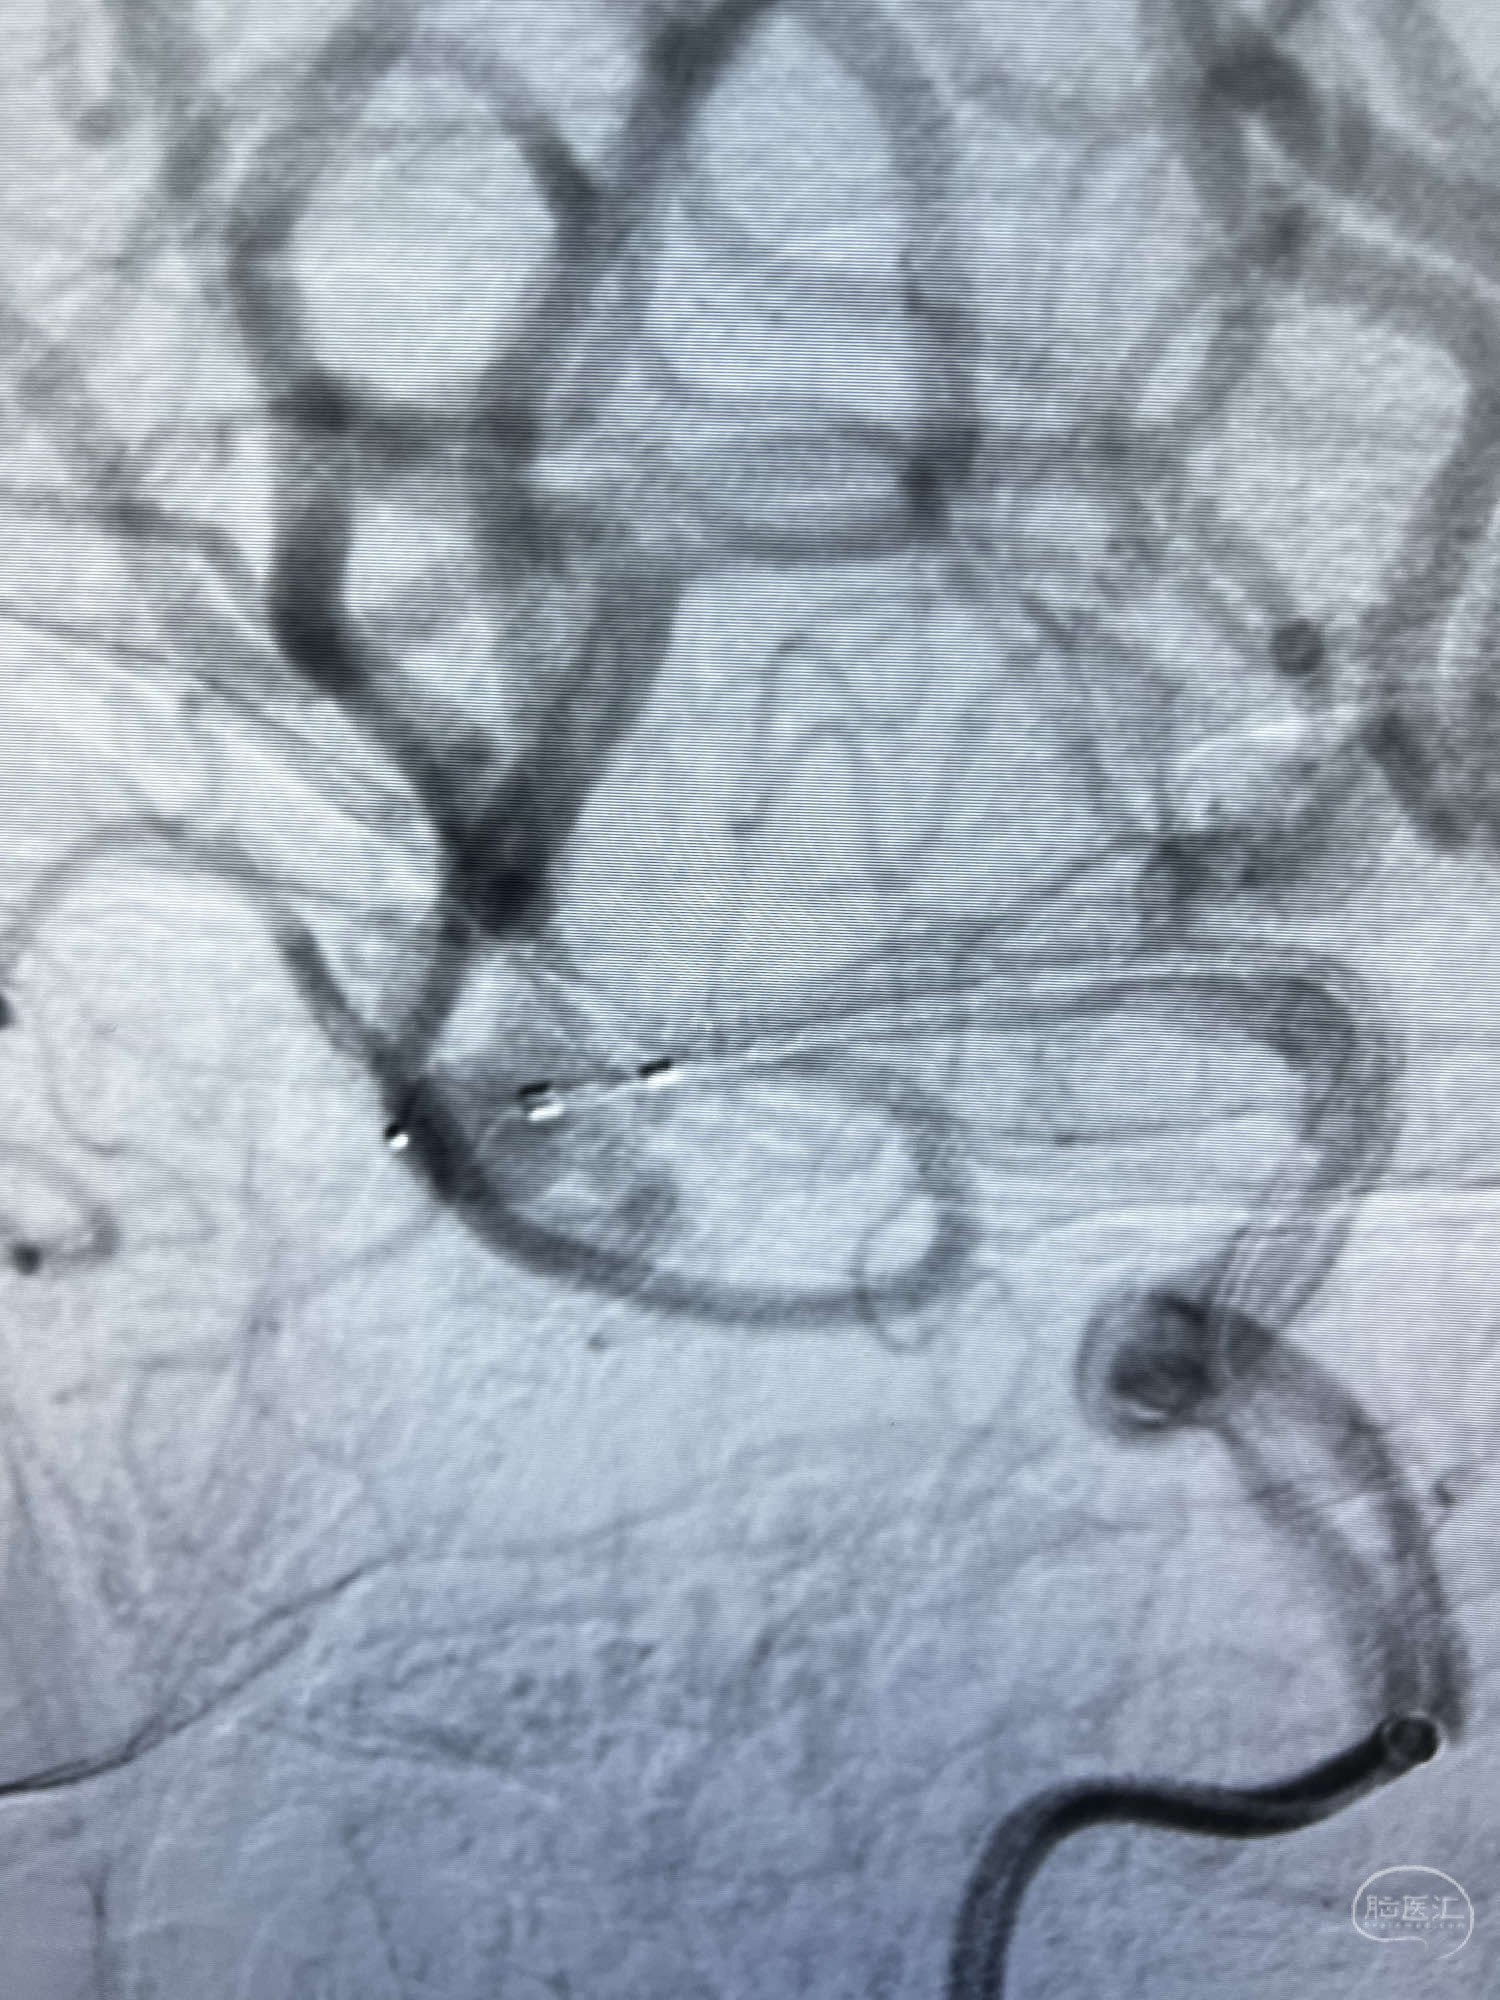

DSA示:左侧颈内动脉眼动脉段以远闭塞,后交通动脉开放,椎基底动脉通过后交通动脉代偿左侧大脑中动脉区域,右侧发出双侧大脑前动脉,右侧大脑中动脉M1末端宽颈动脉瘤,大小约4.3mmx4.6mm。

6F Neuromax➕6F115cm 心玮中间导管建立路径,sychro14微导丝➕VIA21超选至动脉瘤体内近中部,WEB5mmx3mm植入动脉瘤。

WEB瘤内扰流装置5mmx3mm经过“种子、萌芽、开花”三个阶段,打开后良好贴壁,动脉瘤内血液滞留,载瘤动脉通畅。WEB一步到位,通过瘤内扰流的方式起到栓塞动脉瘤的作用,避免了应用支架保护分支血管,简化了操作步骤,降低了术中血栓及出血的风险。